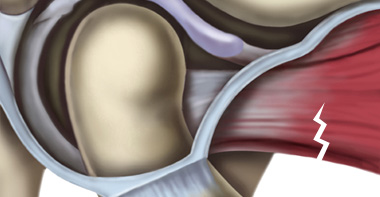

턱관절 디스크가 정상위치보다 앞으로 나와있는 상태입니다. 얼굴뼈와 턱뼈 사이에서 윤활작용을 해야 할 디스크가 앞으로 빠져있기 때문에 입이 잘 벌어지지 않고 입을 벌릴 때 통증을 느끼게 됩니다. 입을 크게 열면 앞으로 빠져있던 디스크가 턱뼈에 걸려 제자리로 돌아가며 ‘딱’하고 소리가 나는 경우와 입을 아무리 벌려도 디스크가 제자리로 돌아가지 못해 소리조차 나지 않는 경우로 나눌 수 있습니다. 얼굴의 근육과 인대 손상은 물론 목의 이상까지 동반하는 경우가 많기 때문에 수개월 이상의 치료가 필요한 경우가 대부분입니다.

디스크 전방전위1

-

입을 다물고 있는 상태

-

입을 열고 있는 상태

입을 열면 디스크가 제자리로

돌아가는 경우

디스크 전방전위2

-

입을 다물고 있는 상태

-

입을 열고 있는 상태

입을 열어도 디스크가 제자리로

돌아가지 못하는 경우